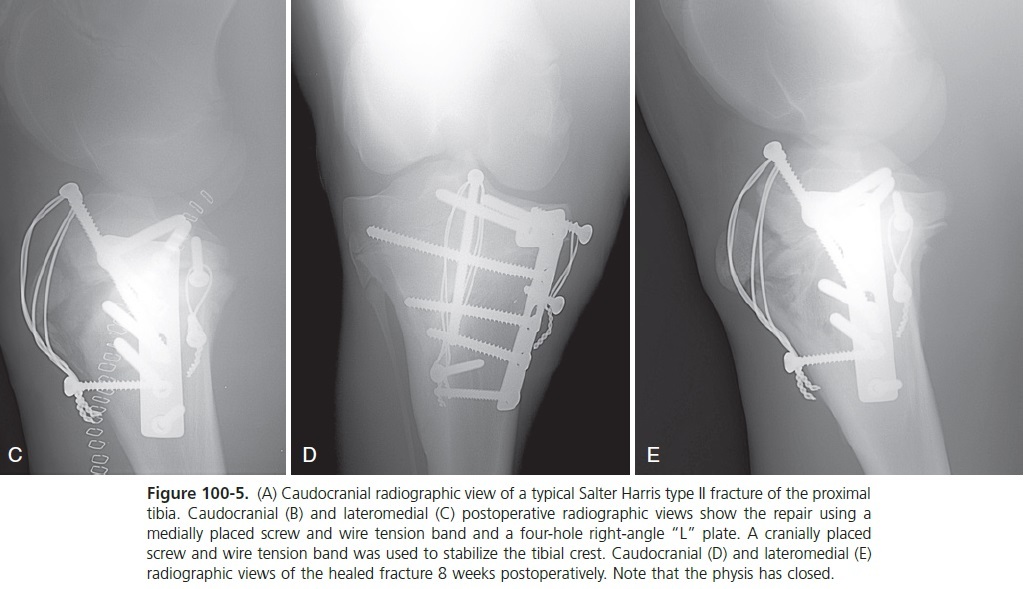

What is the most common type of tibial fracture diagnosed in foals?

Salter-Harris type II proximal physeal fracture

(A) Caudocranial radiographic view of a typical Salter Harris type II fracture of the proximal tibia.

What type of force creates proximal physeal fractures in foals?

Medial tension force

What is the treatment of choice for proximal physeal fractures of the tibia in foals?

Medial plate fixation because it is a medial tension force

Salter harris type II physeal fracture heals in how much time?

3 to 4 weeks

A fter the debris is removed from the fracture, the soft tissue must be elevated along the medial aspect of the proximal tibial physis. If this soft tissue is not elevated, it becomes trapped between the metaphyseal fragment and the physis, preventing complete reduction. Manual downward pressure on the medial aspect of the proximal tibial metaphysis places the intact soft tissue on the lateral aspect of the limb under tension and reduces the fracture. Reduction can be maintained by the placement of one 4.5-mm cortex screw in the epiphysis and one in the metaphysis. A figure-of-eight tension band wire is tightened between the two screws, maintaining reduction during placement of the primary implants if the stability is tenuous (see Figure 100-5, B and C).

The two transverse holes are positioned over the epiphysis closer to the caudal aspect of the proximal tibia, halfway between the femorotibial joint surface and the physis. A right-angle “L” plate with the proximal (short) limb of the plate facing craniad and the long limb of the plate distal along the tibia gives the most diaphyseal contact without the plate overhanging the metaphyseal cortex (see Figure 100-5, B and C). The two proximal screws are inserted across the width of the epiphysis. The screws should be oriented as much as possible parallel to the caudal cortex in a transverse plane, not perpendicular to the plate. The use of 5.5-mm cortex screws is ideal in the epiphysis. The distal screws in the plate are inserted into the metaphysis after using the tension device or are placed in the load position to achieve axial compression.

The new veterinary 4.5/5.0-mm LC P T-plate is ideal for this application (see Figures 77-40 and 100-6, A to D). If an LC P is used, the fracture is reduced, and the locking head screws are placed in the epiphysis first, followed by axial compression of the fracture using a 5.5-mm cortex screw in the load position and finally implantation of the remaining locking head screws in the metaphysis. The presence of a hole for temporary 2-mm pin insertion through the plate into the epiphysis is useful to guide the proper location of the locking head screws since their angle to the plate is fixed and cannot be manipulated. It is desirable to pass at least one of the plate screws across the proximal metaphysis into the lateral metaphyseal fragment that remains attached to the epiphysis or into the lateral epiphysis. This increases the stability of the lateral aspect of the fracture (see Figures 100-5, B and C, 100-6, D and E). The proximal tibial physis can be bridged with this screw and when the screw is removed the physis will normally resume growing.

Tension-band wire The tibial crest remains attached to the epiphysis and is under continual cyclic tension from the patellar tendon attachments. Neutralization of this force greatly aids stability. The most stable fixation is achieved with a tension-band wire used to stabilize the tibial crest. A 5.5-mm cortex screw is placed from proximal to distal through the epiphysis and into the metaphysis to act as the proximal anchor for the tension-band wire. A distal screw in the metaphysis or a hole through the cranial aspect of the metaphysis is used for the distal anchor of the tension band. One or two strands of 1.5-mm wire are placed in “figure-of-eight” fashion and twisted to tighten the construct (see Figures 100-5, B and C, and 100-6, C and D). Alternatively, a 1-mm cable can be substituted for the wire. The proximal screw is left above the bone surface under the patellar ligaments and not tightened down to the surface of the bone to allow removal at a later date.

If the 4-week follow-up radiographs indicate healing, exercise is increased over the next month to unrestricted exercise by 8 weeks. If no complications are encountered and the physis has not closed, the implants can then be removed after 8 weeks to allow the physis to resume growth if growth potential remains (see Figures 100-5, D and E, and 100-6, E).